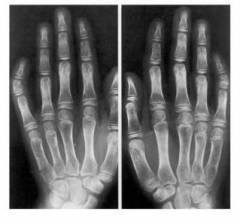

Искривление пальцев

Искривление пальцев может быть признаком различных врожденных патологиях. При хромосомных аномалиях этот симптом затрудняет диагностику. Например, при синдроме Шерешевского-Тёрнера изменения в кистях рук фиксируются в 75% случаев. Обнаружить эти симптомы сразу после рождения сложно, так как многие деформации становятся заметными только с возрастом.

Наиболее распространенные изменения:

- клинодактилия мизинца (искривление в сторону безымянного пальца);

- укорочение пястных костей (ладонь шире и короче);

- укорочение IV и V пальцев;

- уменьшенные ногти;

- синдактилия (сращение пальцев) встречается реже, чем при других хромосомных заболеваниях.